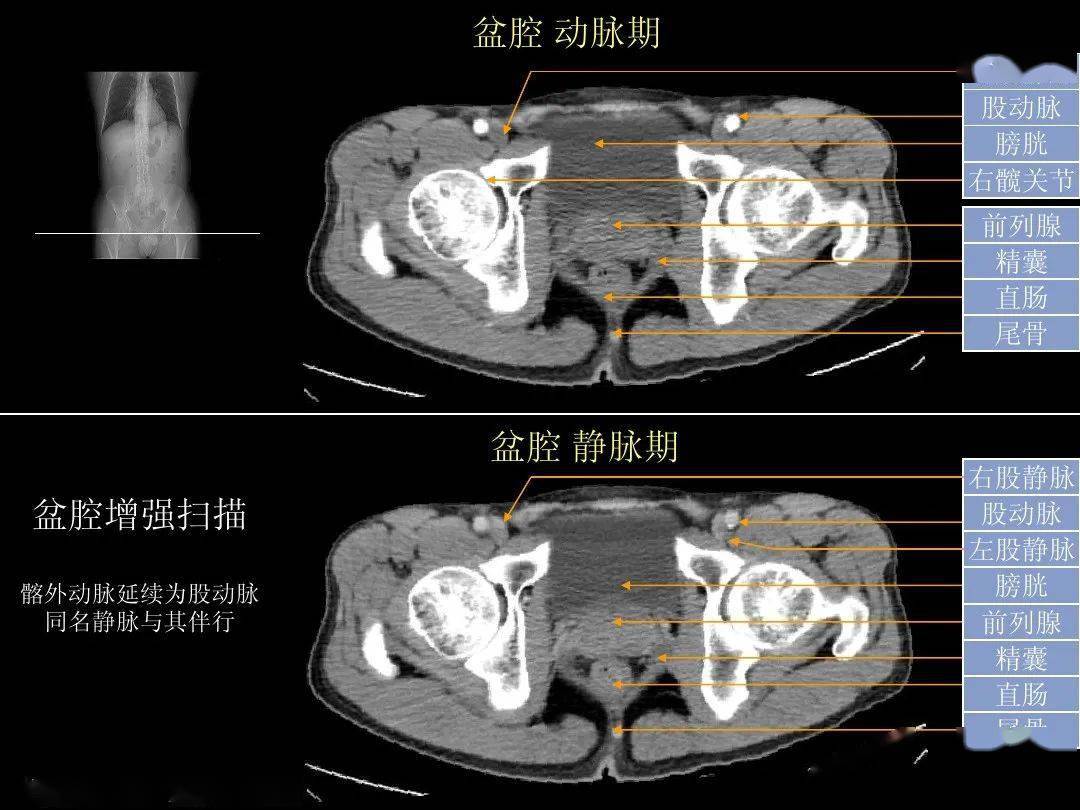

正常男性盆腔ct解剖:膀胱,精囊腺层面